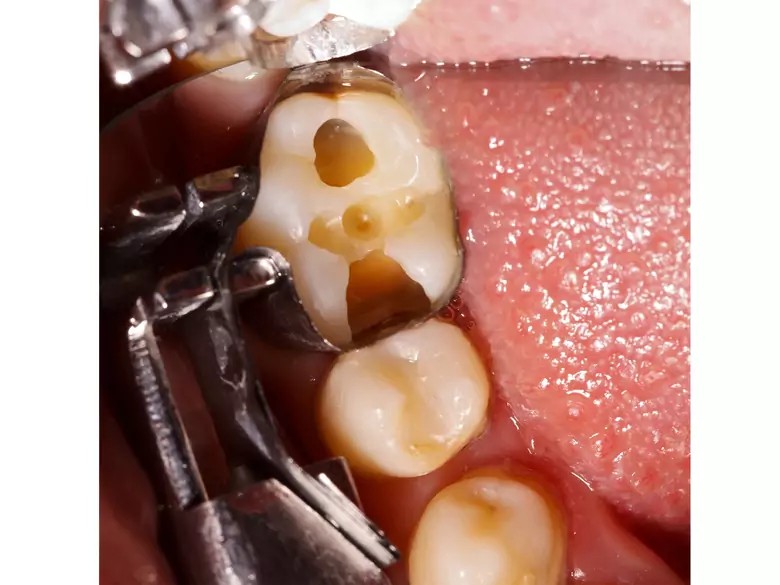

Caries, broken teeth

Arhadectomy is nothing more than a situation where, in order to save an upper molar tooth, it is necessary to cut off and then remove one of the roots of a multi-rooted tooth.